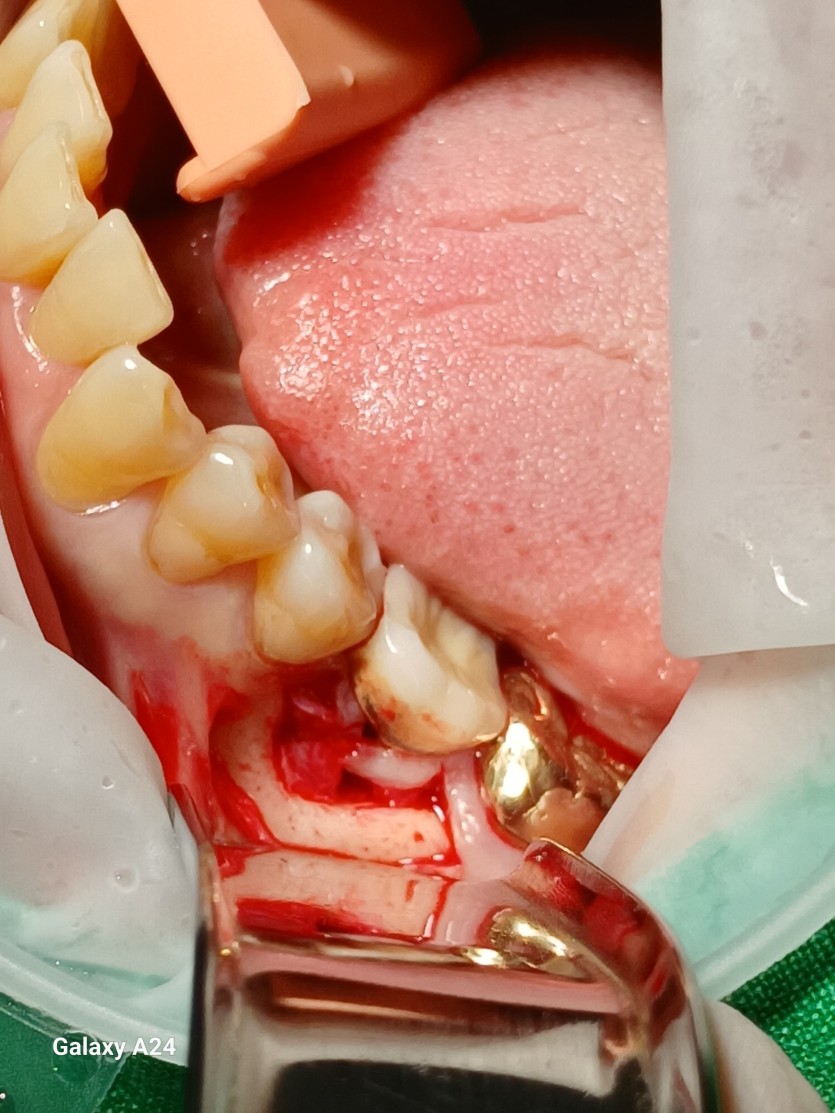

#36 타병원 임플란트 뼈이식 + 재식립